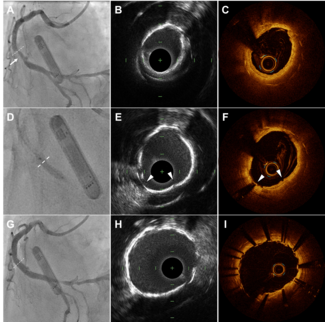

The authors share a case of complex wire entrapment during left anterior descending percutaneous coronary intervention illustrating the role of intravascular ultrasound in directing a bailout strategy.